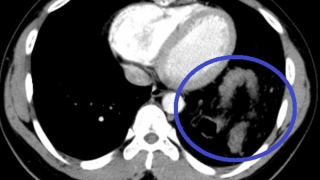

Vỡ cơ hoành khiến đại tràng, dạ dày "chui" lên ngực lại ngỡ hậu COVID-19